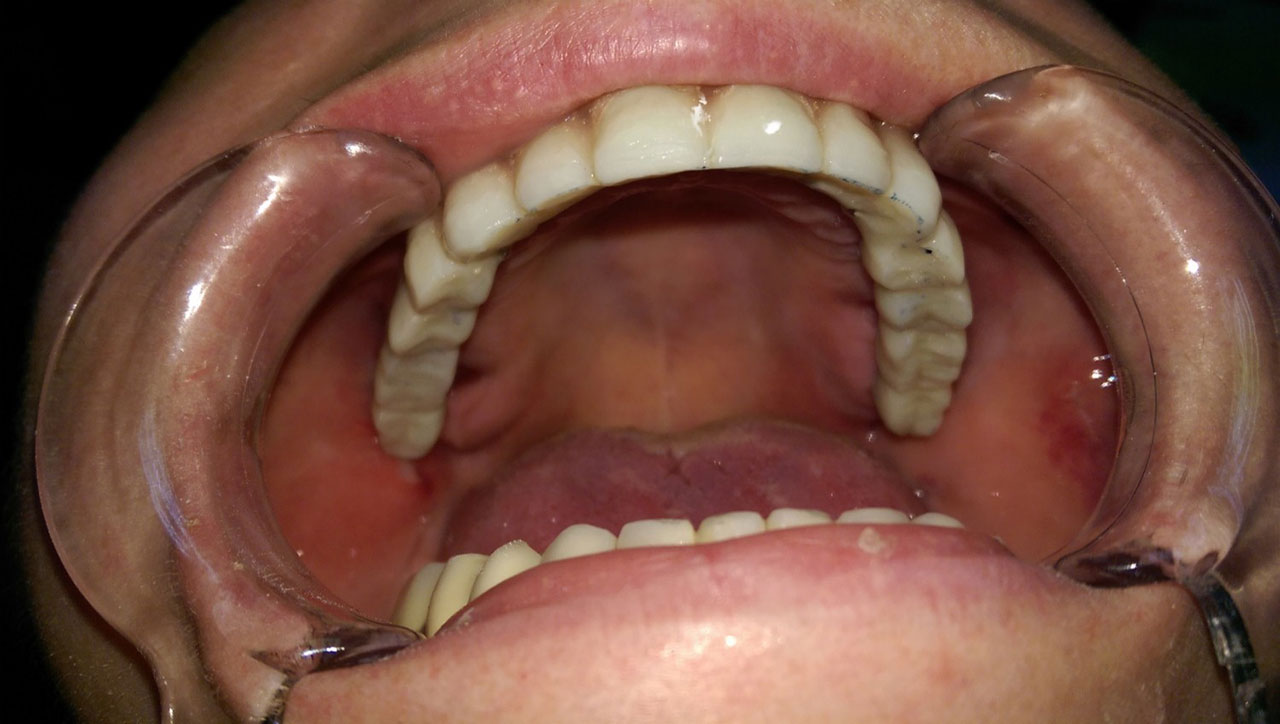

• esettanulmany-11

Szájban a hosszútávú ideiglenes híd.(Fém vázzal erősített műanyag híd.)

• esettanulmany-12

72 órával az alsó-felső állcsont teljes implantációs helyreállítása után, így mosolyog a páciens a beragasztott, fix hidakkal.